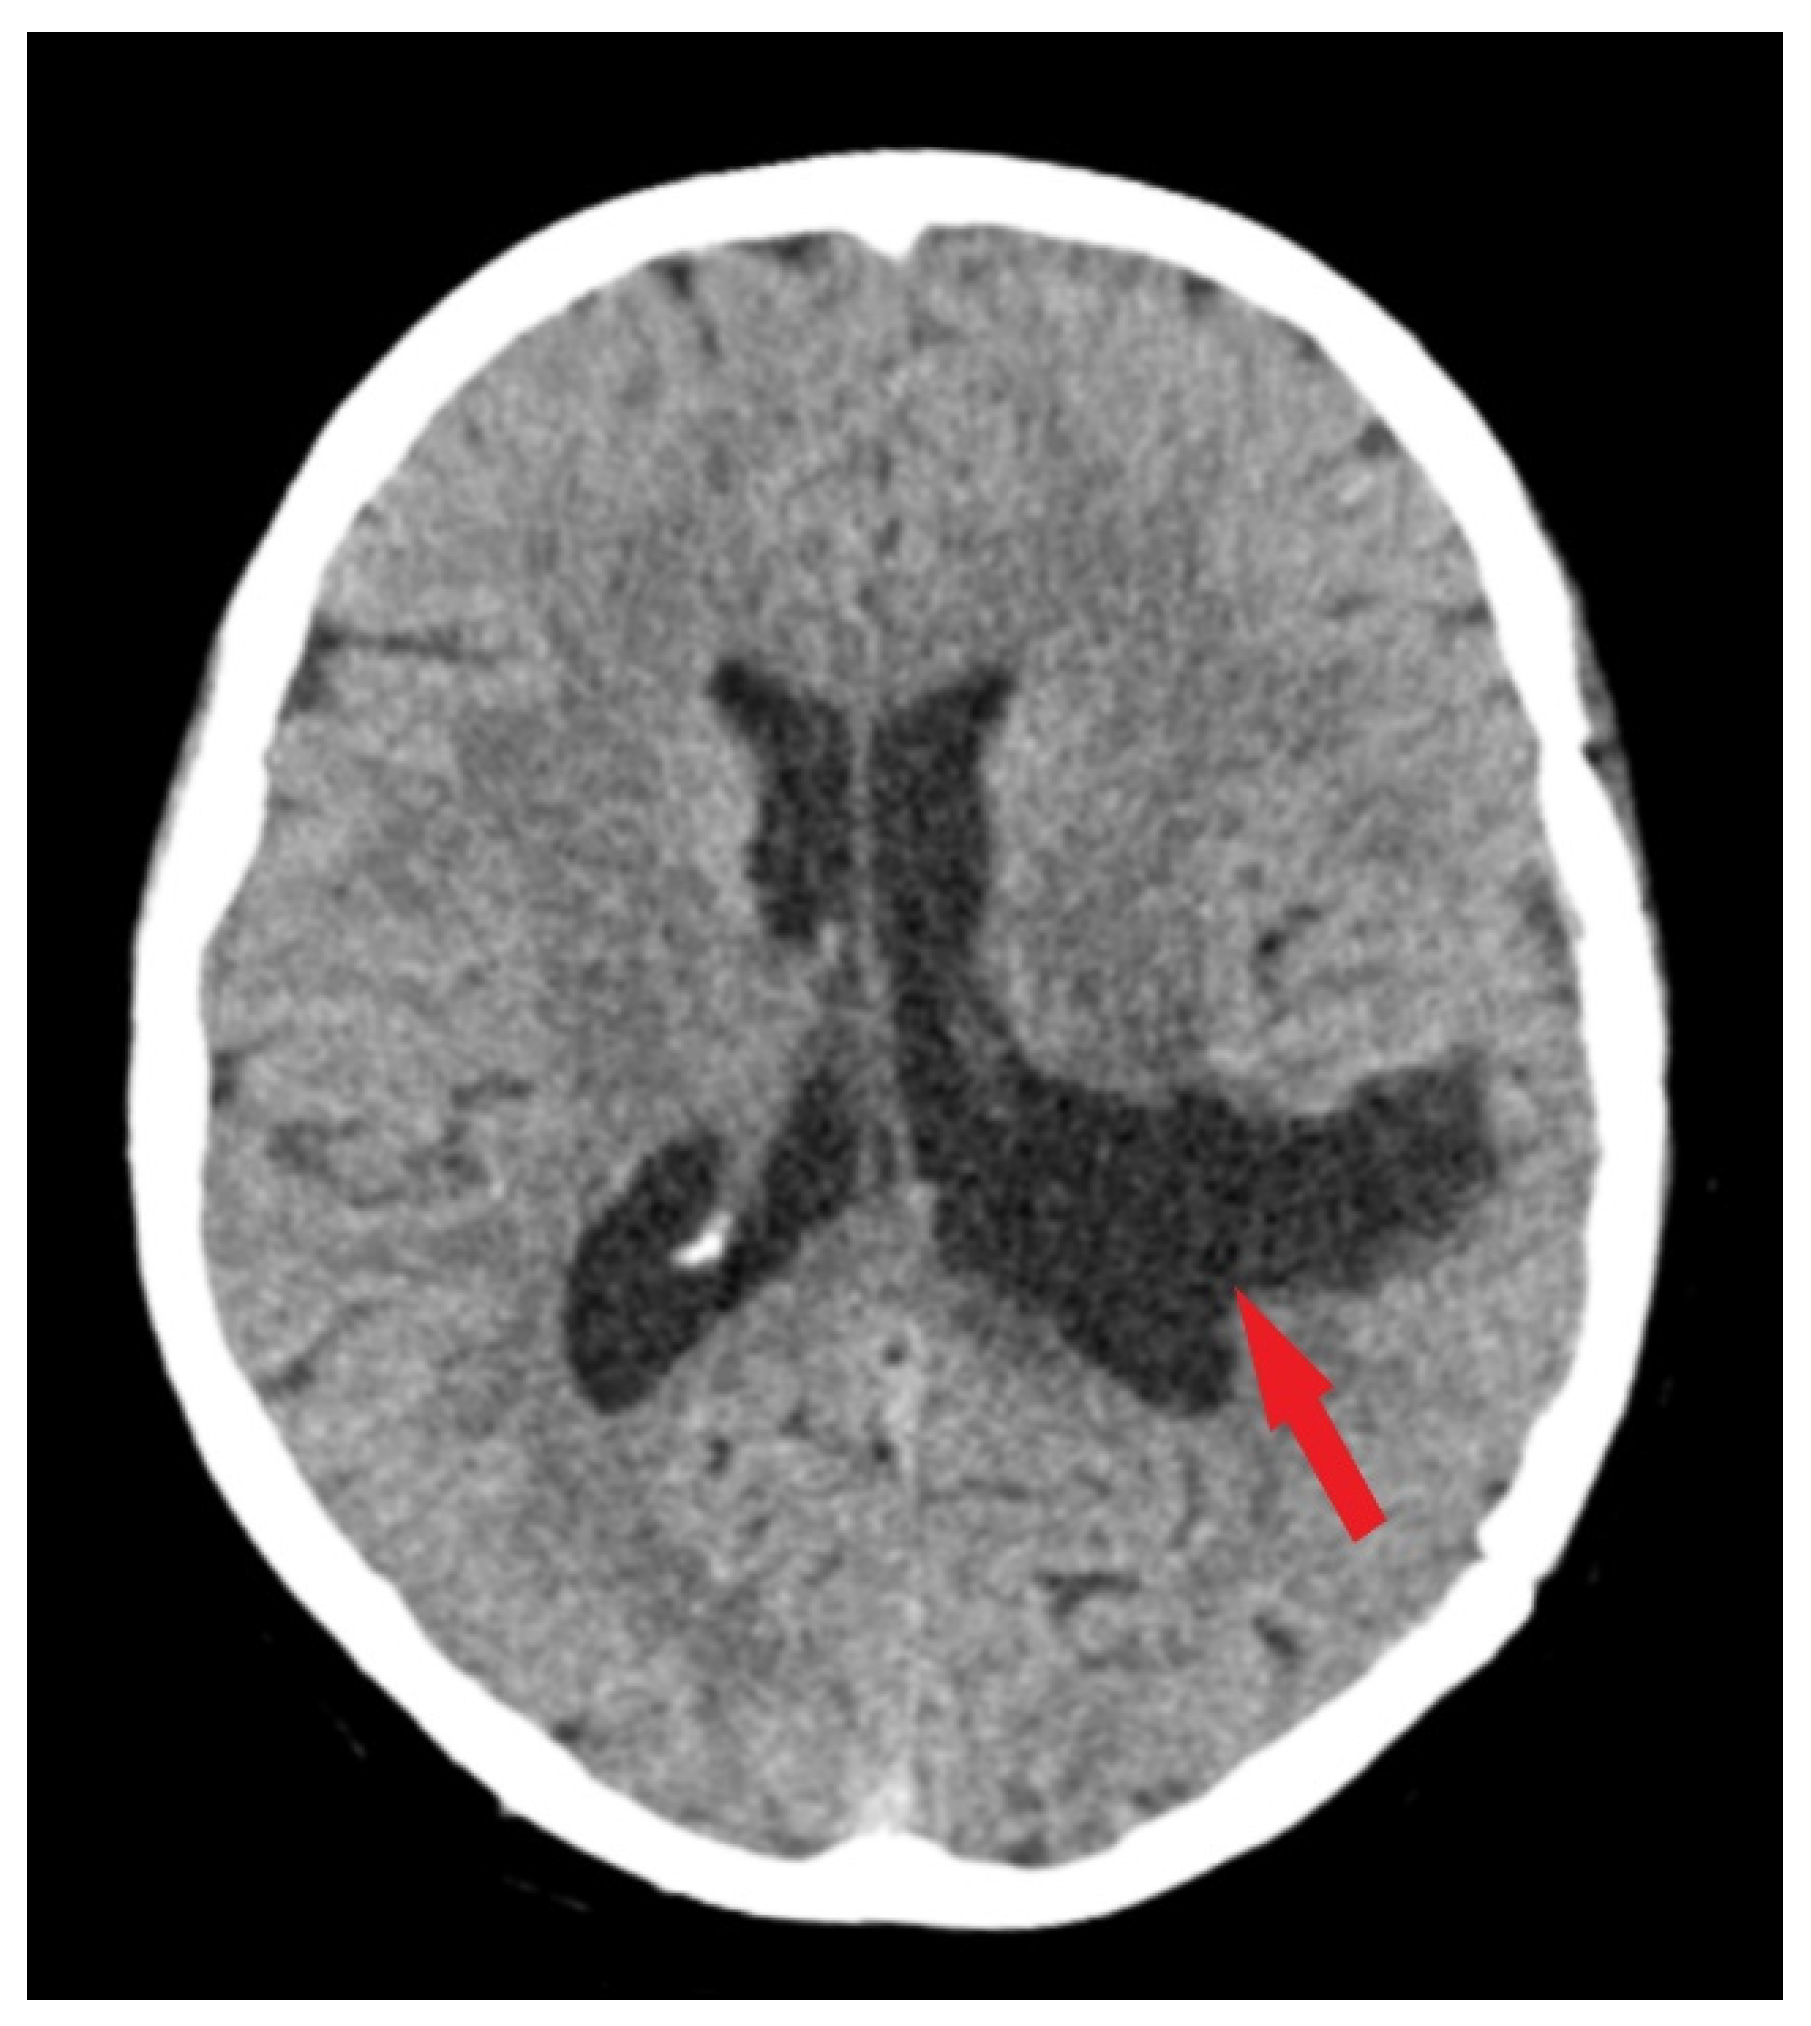

Figure 3.

Postoperative CT scan. Tissue window of CT scan highlights total removal of the intraventricular meningioma (red arrow) with edema remission.